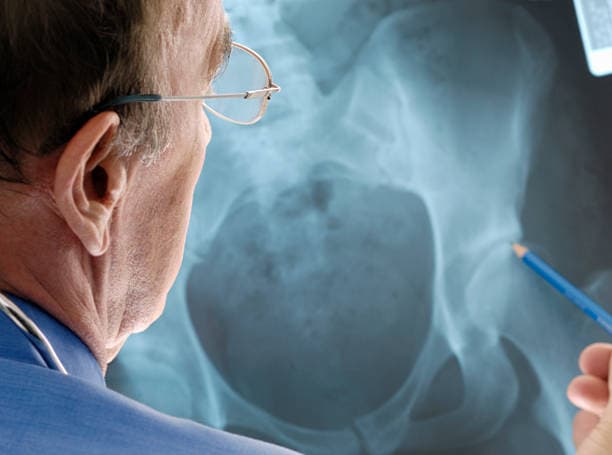

Hip arthroplasty procedure steps

Preoperative Preparation: Before the surgery, patients undergo a comprehensive evaluation, including a review of their medical history, physical examination, and imaging studies such as X-rays or MRI scans. This helps the surgeon assess the extent of joint damage and plan the surgical approach. Patients are also advised to follow specific preoperative instructions, which may include discontinuing certain medications, fasting, and arranging for postoperative care and assistance.